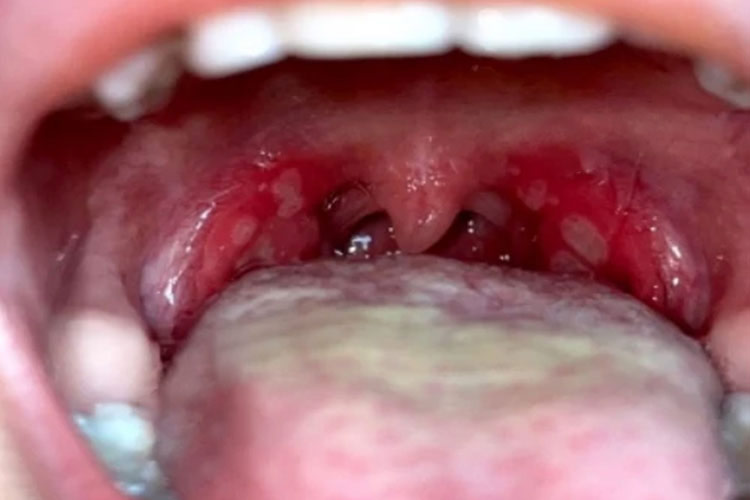

疱疹性咽峡炎表现为发热、咽痛,检查可见咽部充血、疱疹,可破溃形成溃疡。